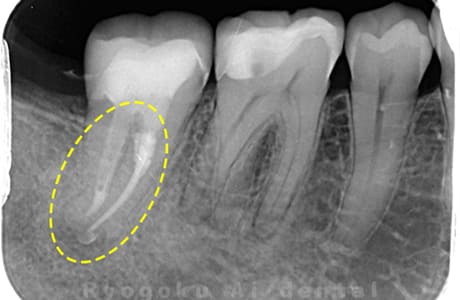

Case02

-

- 原因

- 慢性根尖性歯周炎

- 治療期間

- 3ヶ月

- 治療内容

- マイクロエンド

- 治療費用

- 121,000円

噛むと痛みが出る、とのことで来院した患者様です。他院での根管治療を終えてましたが、根尖病変を認めるため、マイクロエンドを行いました。